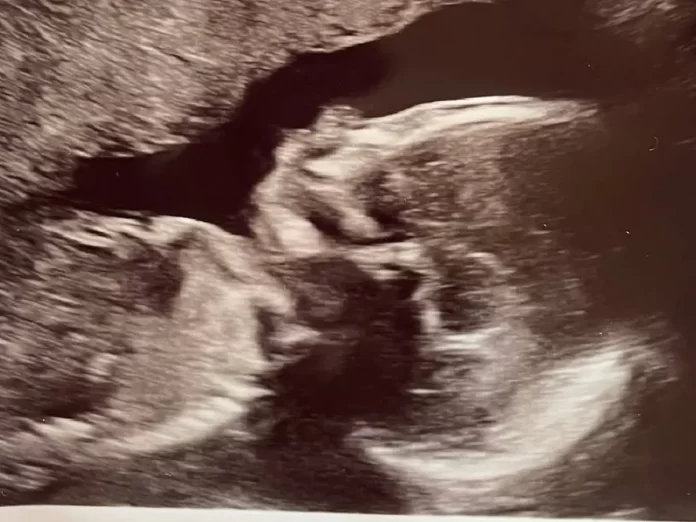

The baby was born November 7 and is currently on a ventilator awaiting surgery for a rare congenital defect known as Transposition of the Great Arteries (TGA) — a condition in which the heart’s two main arteries are reversed. The defect prevents oxygen-rich blood from reaching the rest of the body without surgical correction.

Fire department officials said the baby remains under intensive care as doctors prepare for an open-heart procedure to repair the defect.